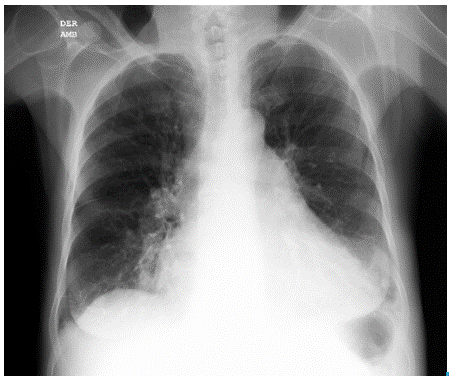

Initial studies included total blood count (normal), electrolytes (sodium:137 mEq/Lt, potassium: 3.82 mEq/Lt, chlorine:103 mEq/ Lt), urine test (normal), arterial blood gases interpreted at 560mmHg atmospheric pressure, which showed a chronic compensated respiratory acidosis without oxygenation disorder (pH 7.38; partial pressure of carbon dioxide (pCO2): 38.9mmHg; bicarbonate (HCO3): 23.6 mE-q/L; base excess: -1.7; oxygen partial pressure (pO2): 95.1mmHg; ratio PaO2/FiO2: 297, lactate 0.8 mmol/L), creatinine and blood ureic nitrogen (1.1 mg/dl and 29.25 mg/dl, respectively). Chest radiography showed an increased cardiothoracic index and signs of pre-capillary pulmonary hypertension (Figure 2a and 2b).

A chronic pulmonary pathology was considered as a probably diffuse interstitial process -based on the findings related to nasal telangiectasias, sclerodactyly, Raynaud phenomenon and on the radiographic evidence of pulmonary hypertension (classified as type I)- due to limited systemic scleroderma (or CREST syndrome), which along with incomplete cholestasis, elevated transaminases and pruritus, increases the possibility of an overlapping primary cirrhosis.

A chest radiograph showed increased cardiothoracic index, sign of pre-capillary pulmonary hypertension, which was confirmed by high-resolution computed tomography (HRCT); no pulmonary fibrosis was found. Also, HRTC was compatible with pneumonia in the antero-basal segment of the lower left lobe, with pleural and pericardial effusion. A sputum smear was performed searching for M. tuberculosis, but it yielded negative results.